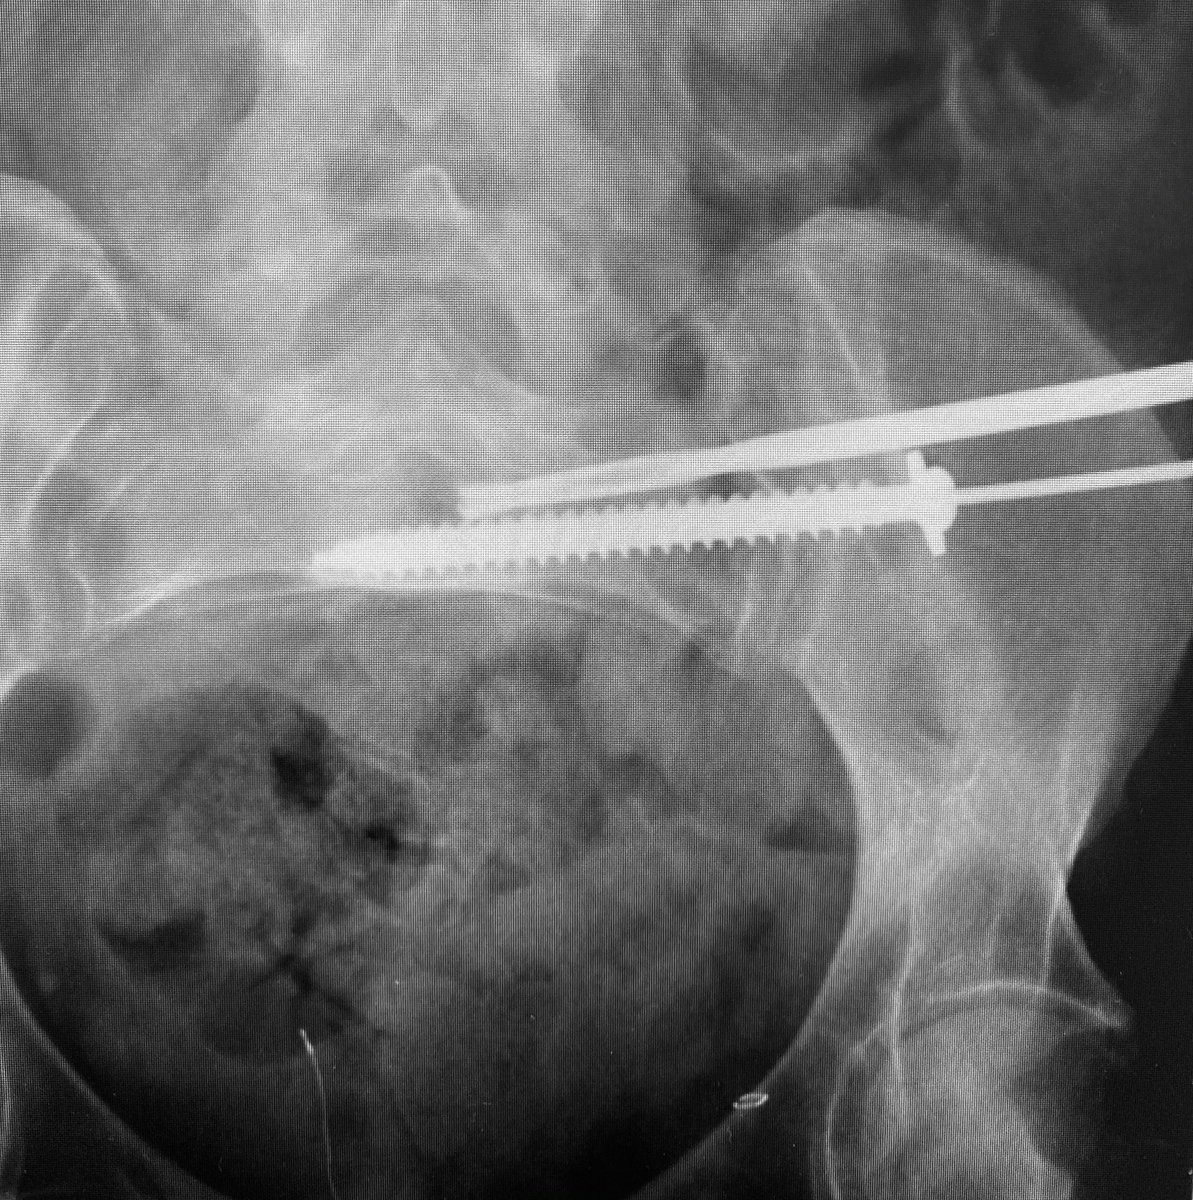

Control your iliosacral screw insertion precision by using an initial K wire to simply identify the optimal insertion site for your intended pathway-insert it 1-2cms then proceed directly to using the cannulated drill - the drill allows early slight corrections without deformity

Use the cannulated drill to avoid wayward misdirections from more flexible guide wires